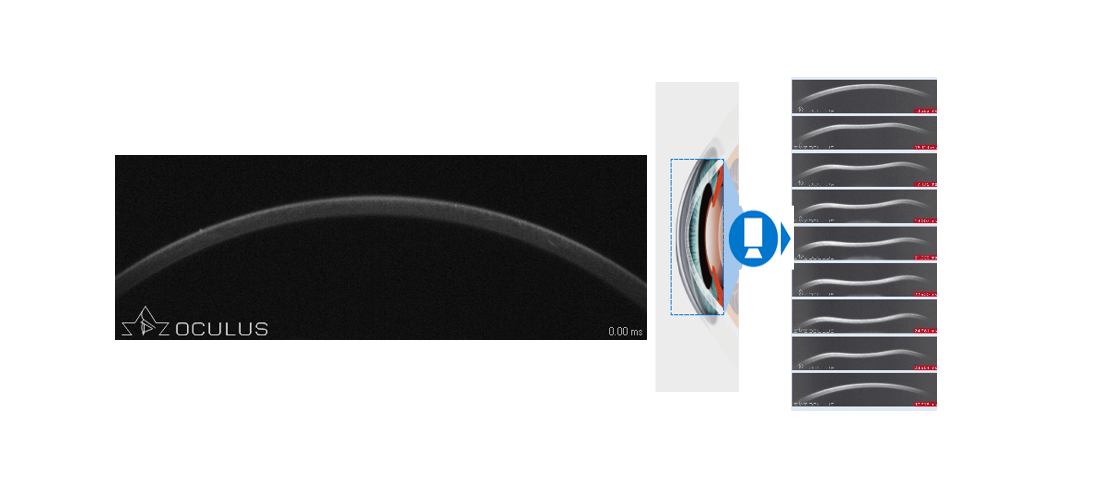

角膜生物力學檢查的作用,就是精準識別這些“隱匿性”風險。Corvis? ST采用Scheimpflug超高速相機(每秒4330幀),在31毫秒內捕捉140幅圖像,完整記錄角膜受氣流沖擊后的凹陷、變形到復原的全過程,實時分析硬度參數(shù)、生物力學校正眼壓(bIOP)等關鍵指標。結合PENTACAM的三維斷層地形圖,實現(xiàn)“動靜結合”的圓錐角膜篩查,極大提升了術前評估的準確性。